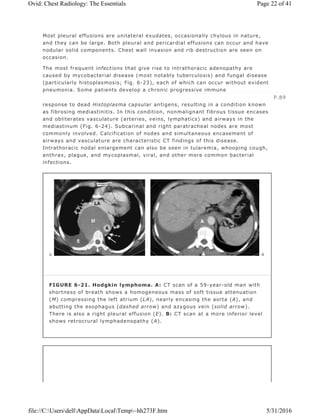

FIGURE 6-21. Hodgkin lymphoma. A: CT scan of a 59-year-old man with

shortness of breath shows a homogeneous mass of soft tissue attenuation

(M) compressing the left atrium (LA), nearly encasing the aorta (A), and

abutting the esophagus (dashed arrow) and azygous vein (solid arrow).

There is also a right pleural effusion (E). B: CT scan at a more inferior level

shows retrocrural lymphadenopathy (A).